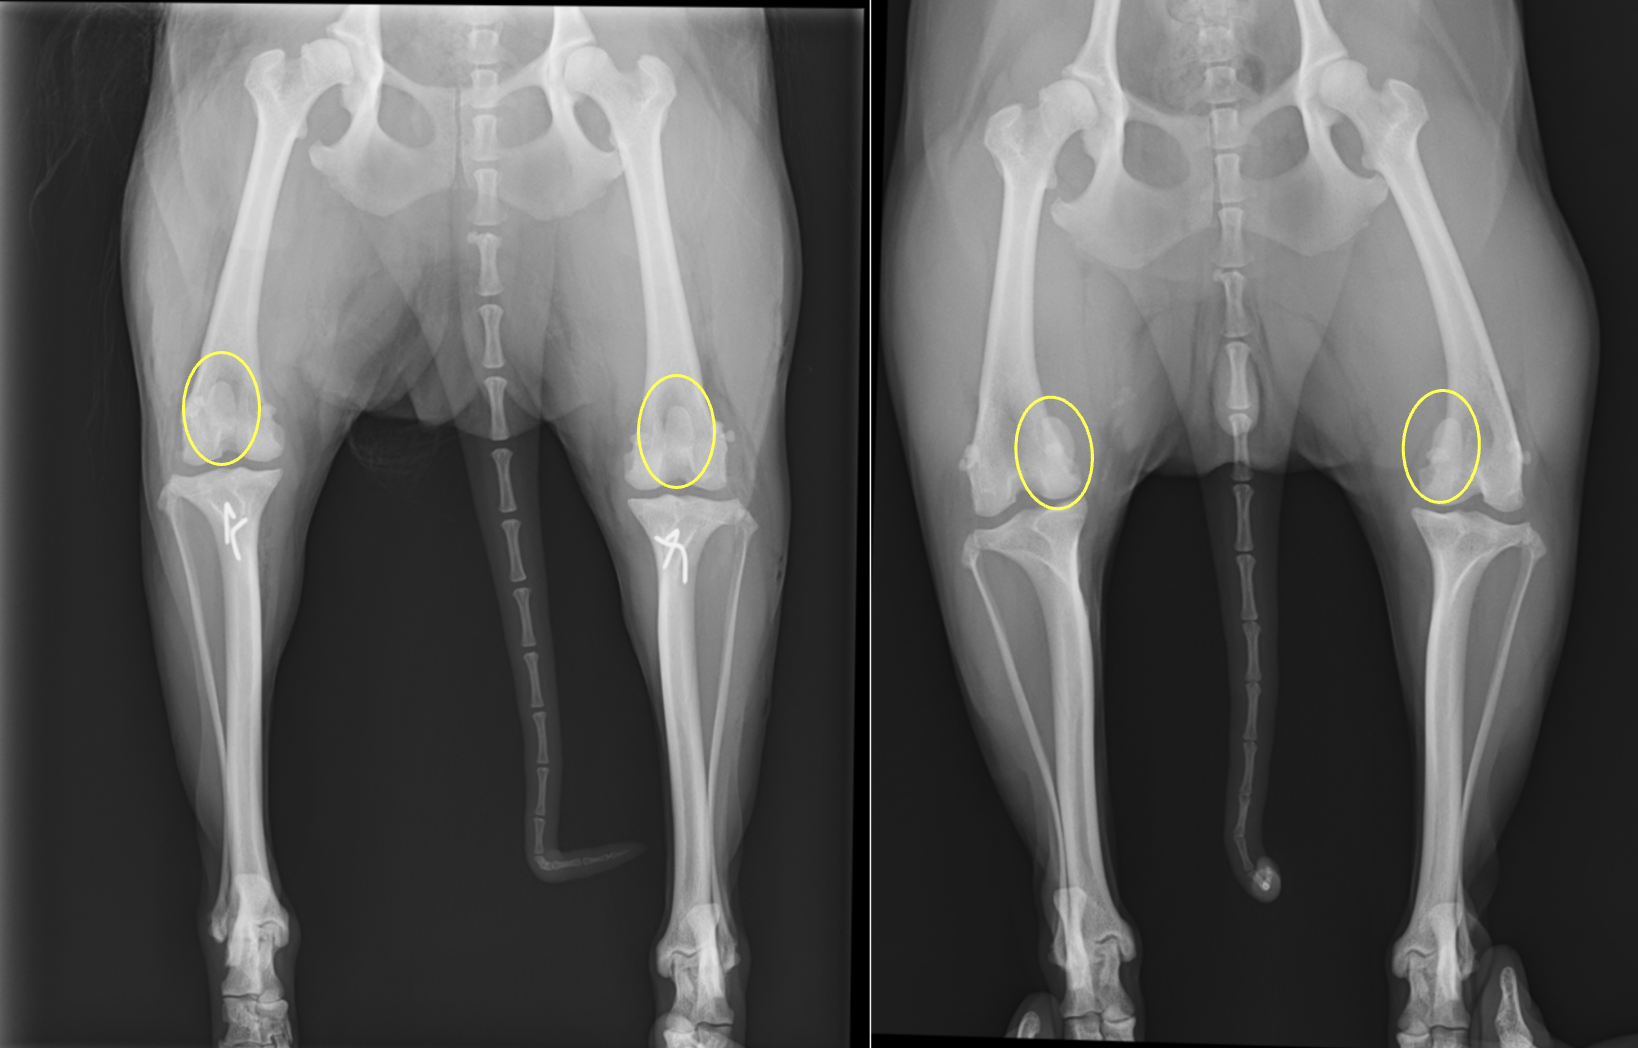

そのため、理想的には関節炎がなるべく少ない時期、つまり脱臼回数が少ないタイミングで外れないようにしてあげることが、関節炎を予防するために最も良い方法となります。 治療法には大きく分けて、内科療法と外科療法の二つに分かれますが、根本的な治療は外科療法となります。 外科には ①滑車溝形成術(溝を深くする) ②内側支帯リリース術(内側の筋肉や靭帯を緩める) ③外側支帯縫縮術(外側の筋肉や靭帯を縫い縮める) ④脛骨粗面転移術(パテラがくっついてい脛骨粗面というところを外側にずらす) ⑤内旋制動術(脛骨が内側に捻じれないように外に引っ張る) などを組み合わせて行われます。Grade4などの重症例に関しては矯正骨きり術と呼ばれる術式が適応となることもあります。

術後は2週間後に抜糸+レントゲン、その後2週間後にレントゲン、1ヶ月後にレントゲン撮影で一旦終了となります。2ヶ月を目処に通常の運動量に戻していきます。両側脱臼の際には両側同時に実施することを推奨しています。